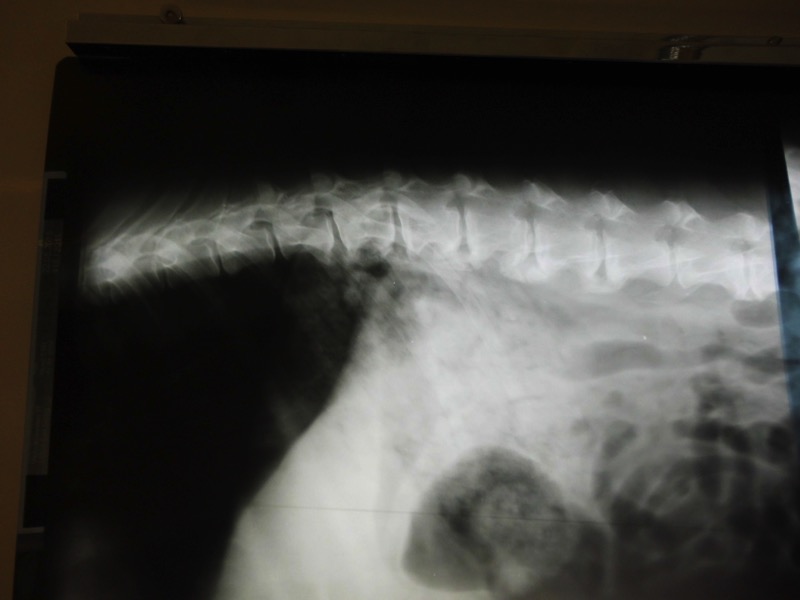

Bei Rolf gibt es leider keine Lösung. Er hat Spondylose, d.h. seine Wirbelsäule ist degenerativ verändert - leider im gesamten Verlauf. Rolf kommt damit klar. Er kann nur nicht mehr mit zu großen sportlichen Aktivitäten belastet werden.